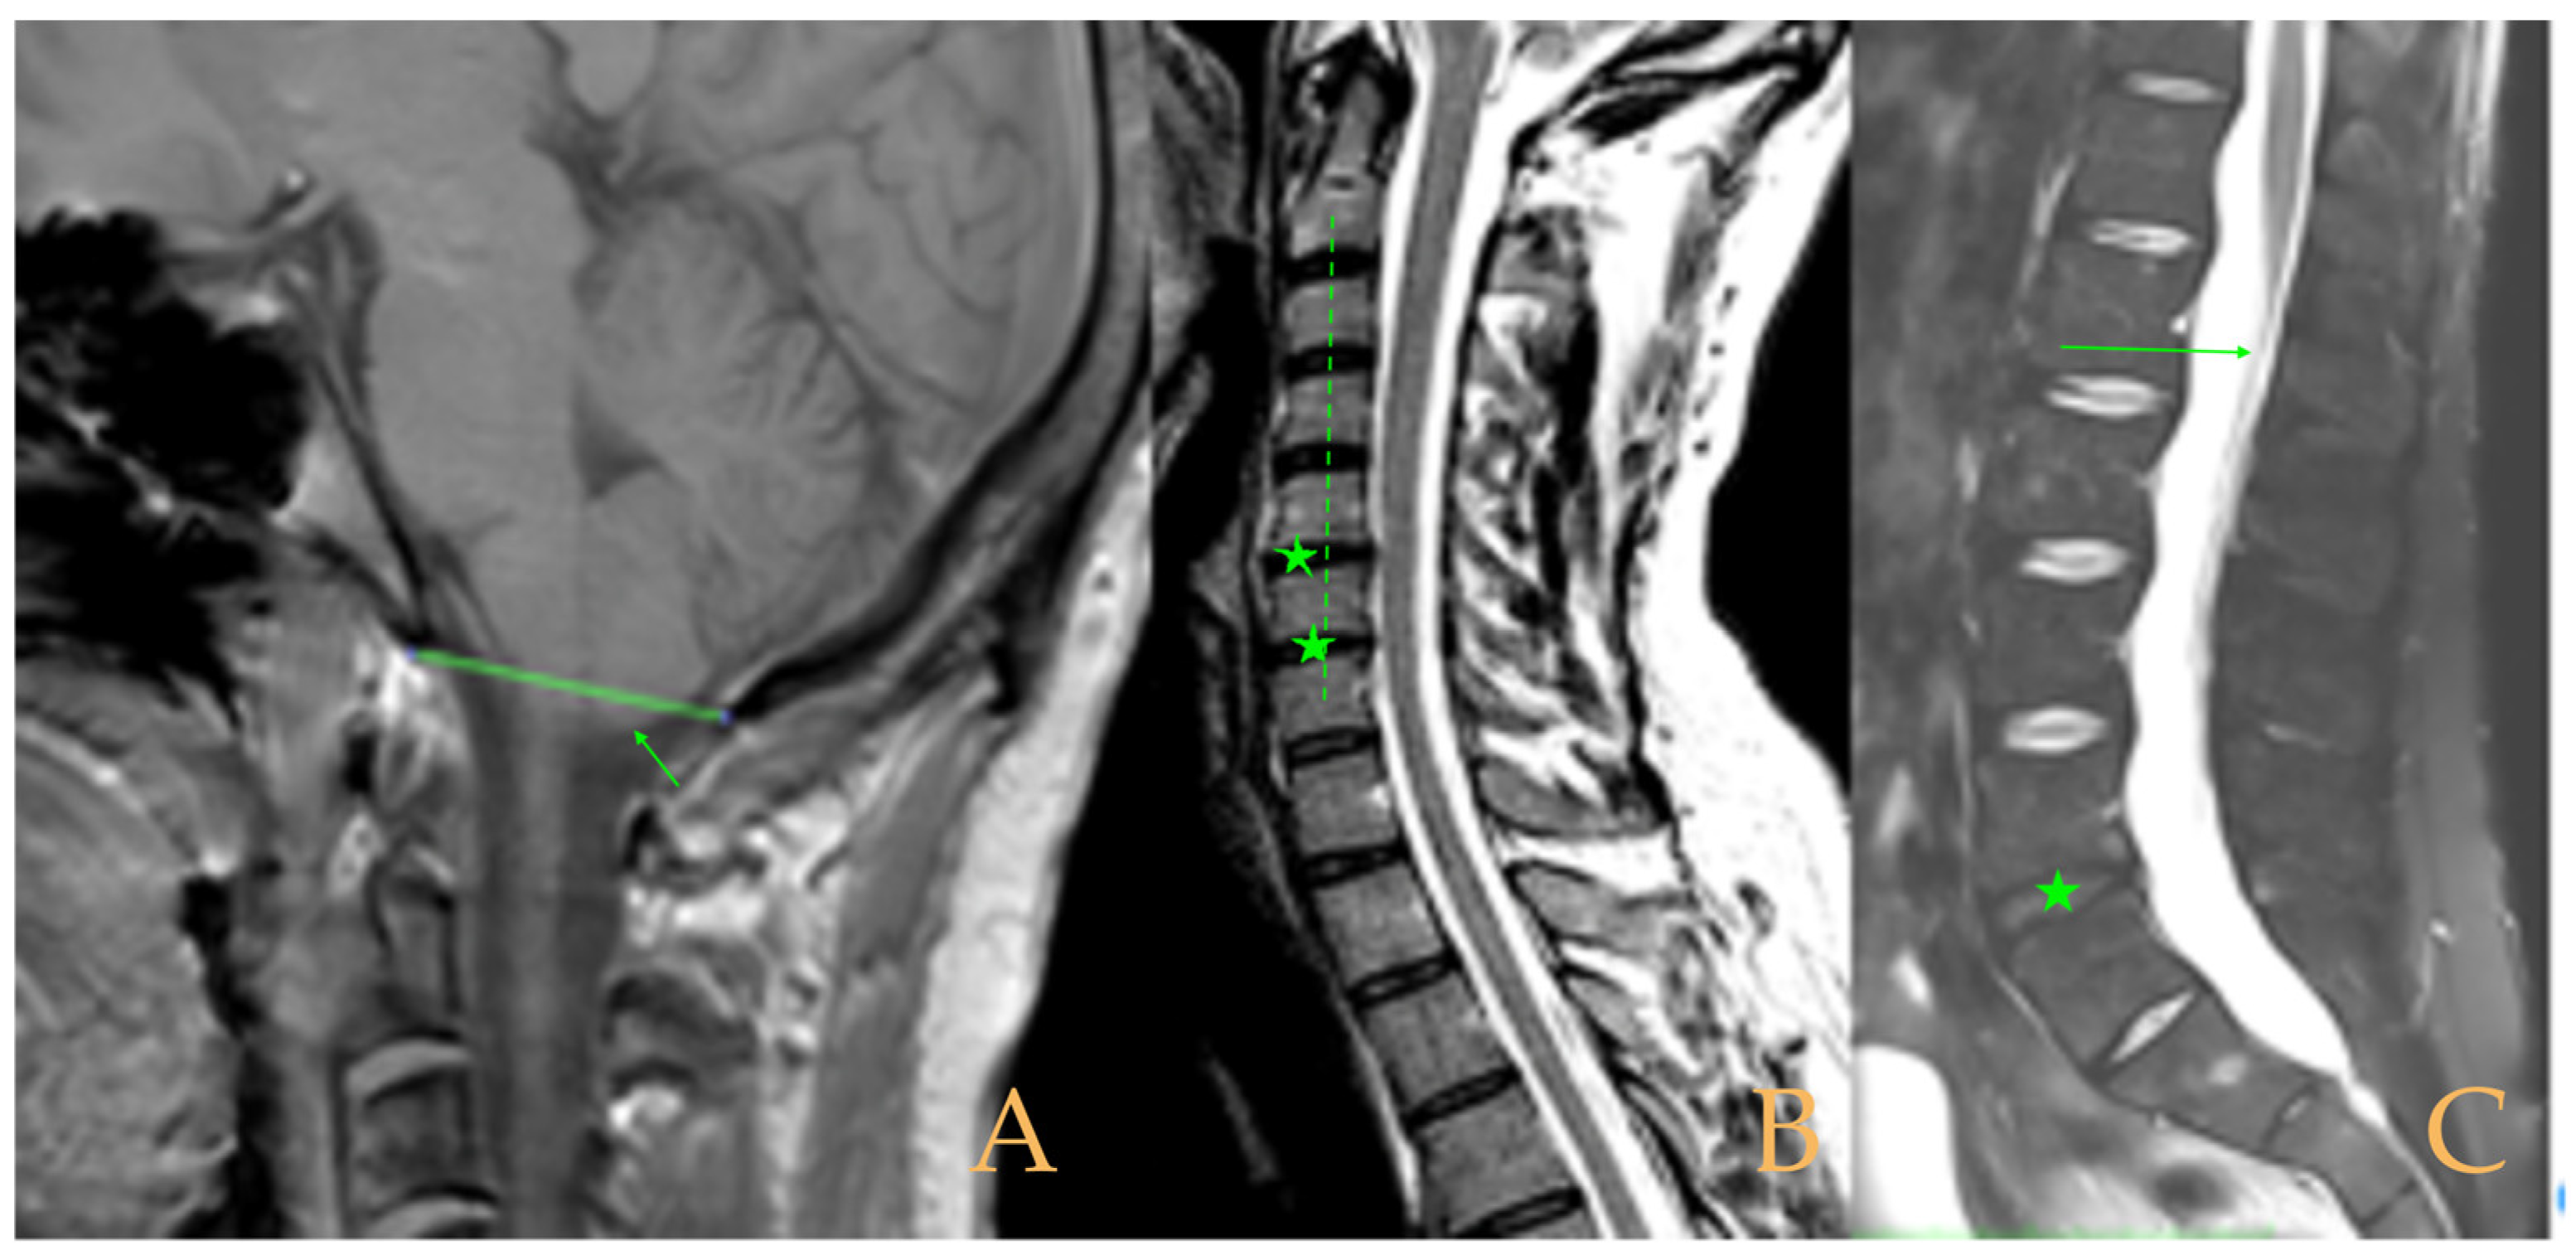

The MRI showed descent of the cerebellar tonsils, increased supracerebral space, and postsurgical repercussions of the sphenoid sinus in the right half. Empty sella turcica. Micro lacunae bilaterally in hemispheres, basal ganglia, and white matter. Straightening of the cervical spine. Cervical spinal cord with tense aspect and inferior lateral displacement, the thoracic portion appears tense with slight ischemia and oedema. Protrusions: C3-C4, C5-C6-C7, T7-T8, and L3-S1. Lumbar hyperlordosis. Sacrococcygeal hyperkyphosis. Ischemia and oedema in epiconus. Low conus medullaris at the level of the upper third of L2 vertebral body. Tarlov cyst at S2 (left) (Figure 4). Proximal filum terminale externum visible. Levoconvex lumbar scoliosis on the spine X-ray estimated at 6°; dextroconvex cervical and thoracic scoliosis estimated at 4°.

The MRI showed descent of the cerebellar tonsils, 13 mm pineal cyst, and multiple disc protrusions in T4-T8 and T9-T10, with herniation T5-T6. Straightening of the thoracic and lumbar spine. Low conus medullaris at the upper third level of the L2 vertebra (Figure 7). The full-spine X-rays showed a mild double-curved thoracic and lumbar scoliosis (<10° Cobb), and lower extremity dysmetria with shortening of the left lower extremity estimated to be 3 mm at the level of the acetabular roofs and 7 mm at the level of the iliac crests. Dextroconvex lumbar scoliosis was estimated to be 2°, and levoconvex cervicothoracic scoliosis was estimated to be 10° (both total, including all vertebrae). The estimated lateral curves, including all vertebral bodies in each region, were cervical lordosis 25°, thoracic kyphosis 34°, and lumbar lordosis 53°.

Figure 4. Imaging of patient 4. A: Cranial MRI with visible descent of the cerebellar tonsils in the foramen magnum (stars); B: cervical MRI with straightening of the cervical spine (interrupted line) and cervical multiple disc disease (arrows); and C: lumbar MRI with conus medullaris at the upper third of L2 (arrow).

Figure 7. Imaging of patient 7. A: Descent of the cerebellar tonsils (star); B: straightening of the cervical spine (interrupted line) with image suggestive of medullar ischemia (arrow); and C: straightening of the upper part of the lumbar spine (interrupted line) and conus medullaris at the level of the upper third of L2 (arrow).